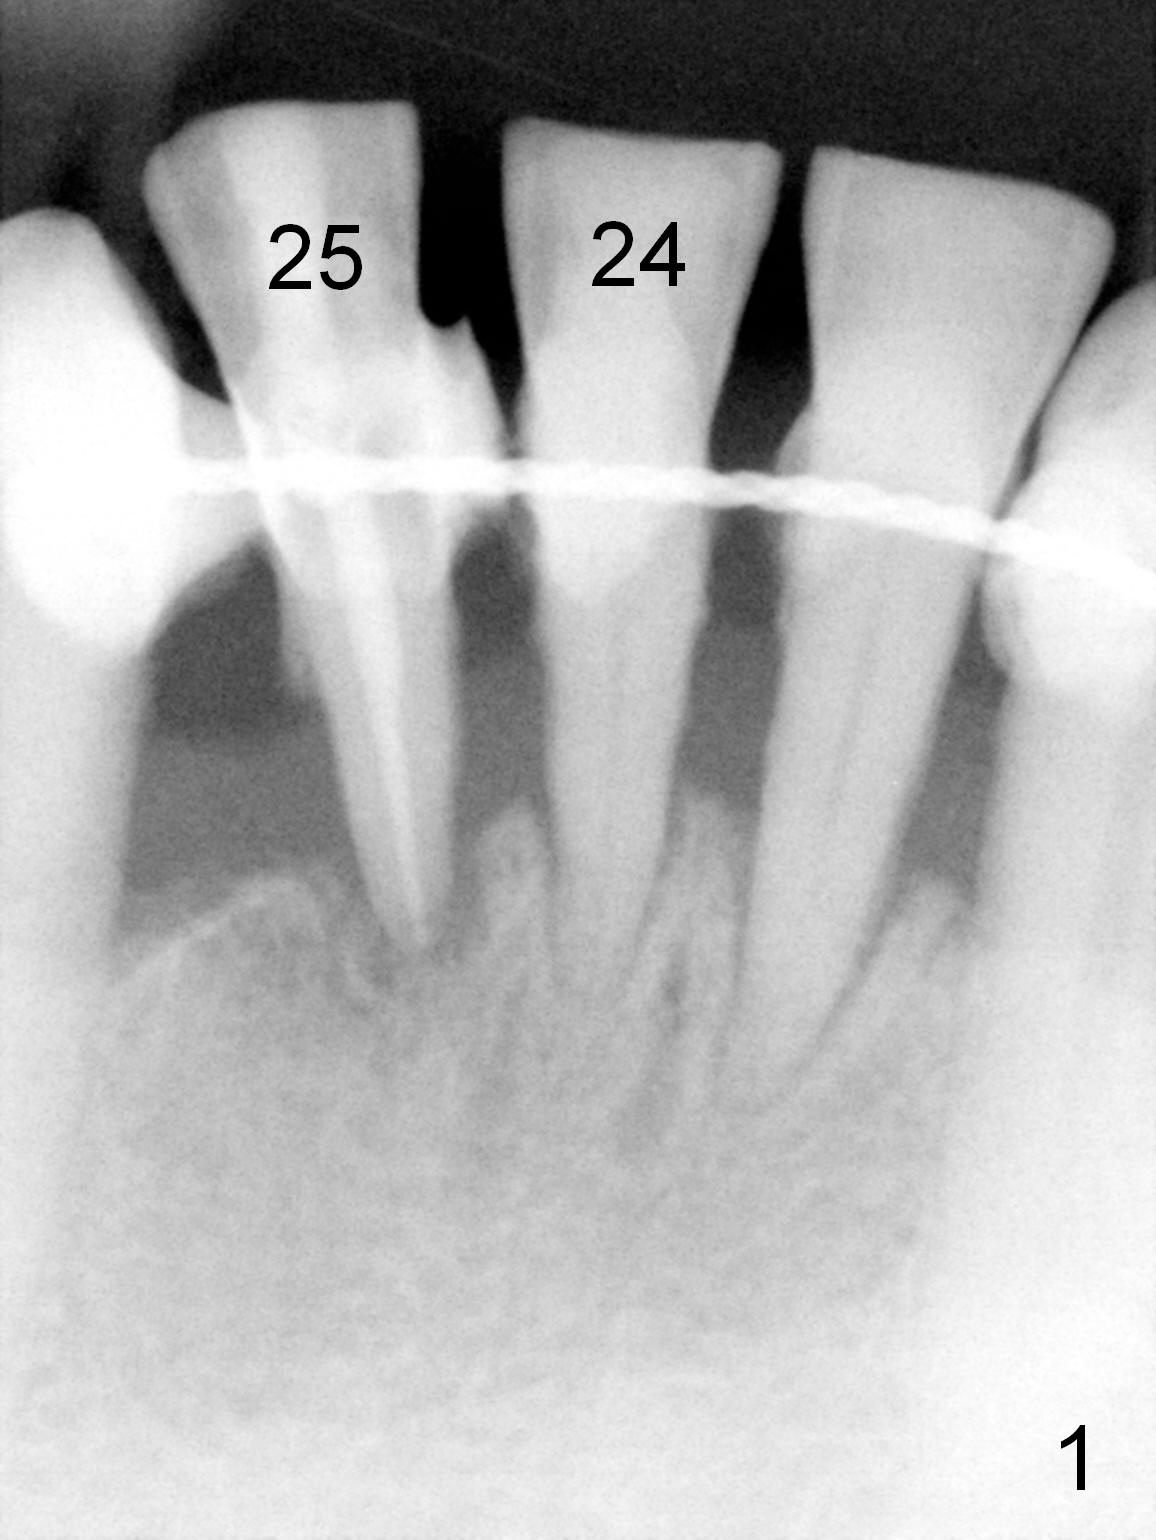

A 59-year-old man requests a partial denture after loss of #24 and 25, seven years after splintng (Fig.1,2).  The remaining incisor (tooth #23) has mobility II.  After discussion, he agrees with implant-supported FPD.  Two of 1-piece implants will be placed at #23 and 25 (Fig.2) to avoid too-close complication.  The first implant will be placed at #25.  The socket of #23 will be treated with Clindamycin.  Surgical and restorative stents are to be fabricated from the model made 7 year earlier (in the shelf of the lab).  Use a 3x14 mm dummy implant for trajectory determination.  Also prepare angled implants.